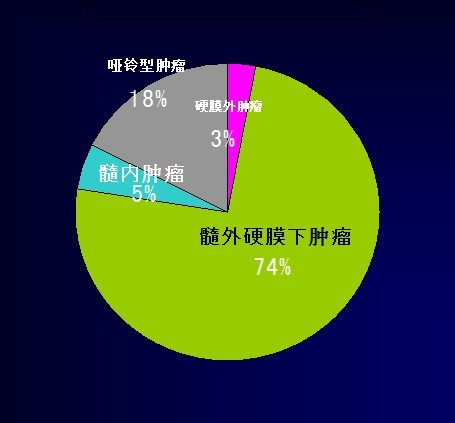

硬膜下髓外肿瘤(intradural extramedullary tumors IDEM):是指发生于硬脊膜下、脊髓外的原发或继发的肿瘤,是椎管内肿瘤中常见的类型,其中以神经鞘瘤和脊膜瘤最为多见。 其它较为少见:室管膜瘤、神经纤维瘤、脂肪瘤、畸胎瘤、血管瘤、蛛网膜囊肿等。

1.椎管内肿瘤中,硬膜下髓外肿瘤约占所有肿瘤的74%;

2.硬膜下髓外肿瘤最常见的为神经鞘瘤(约占67%),其次为脊膜瘤(17%);